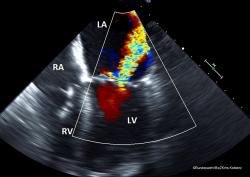

Wir berichten aus Sicht der Anästhesiologie von einem externen Einsatz des herzchirurgischen Teams samt Mobilisierung von Großgerät zur Versorgung eines nicht transportfähigen Patienten mit Herzperforation im Vorhofbereich.